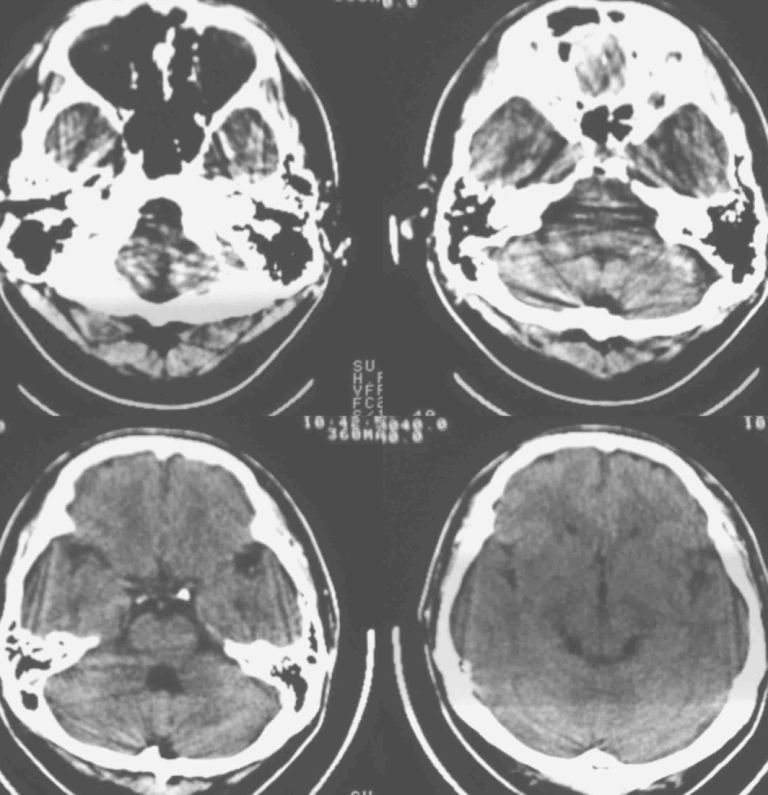

男37岁头持续性痛1天。右额部蛛网膜下腔囊肿诊断是否正确,请老师们帮忙看看。谢谢!

支持右额区蛛网膜囊肿。

有顶叶蛛网膜下腔囊肿

右侧额叶蛛网膜囊肿。